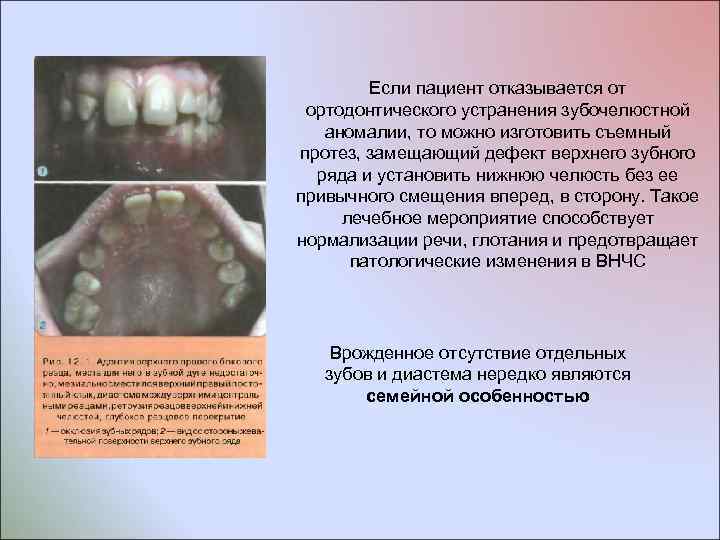

Если пациент отказывается от ортодонтического устранения зубочелюстной аномалии, то можно изготовить съемный протез, замещающий дефект верхнего зубного ряда и установить нижнюю челюсть без ее привычного смещения вперед, в сторону. Такое лечебное мероприятие способствует нормализации речи, глотания и предотвращает патологические изменения в ВНЧС Врожденное отсутствие отдельных зубов и диастема нередко являются семейной особенностью

Если пациент отказывается от ортодонтического устранения зубочелюстной аномалии, то можно изготовить съемный протез, замещающий дефект верхнего зубного ряда и установить нижнюю челюсть без ее привычного смещения вперед, в сторону. Такое лечебное мероприятие способствует нормализации речи, глотания и предотвращает патологические изменения в ВНЧС Врожденное отсутствие отдельных зубов и диастема нередко являются семейной особенностью